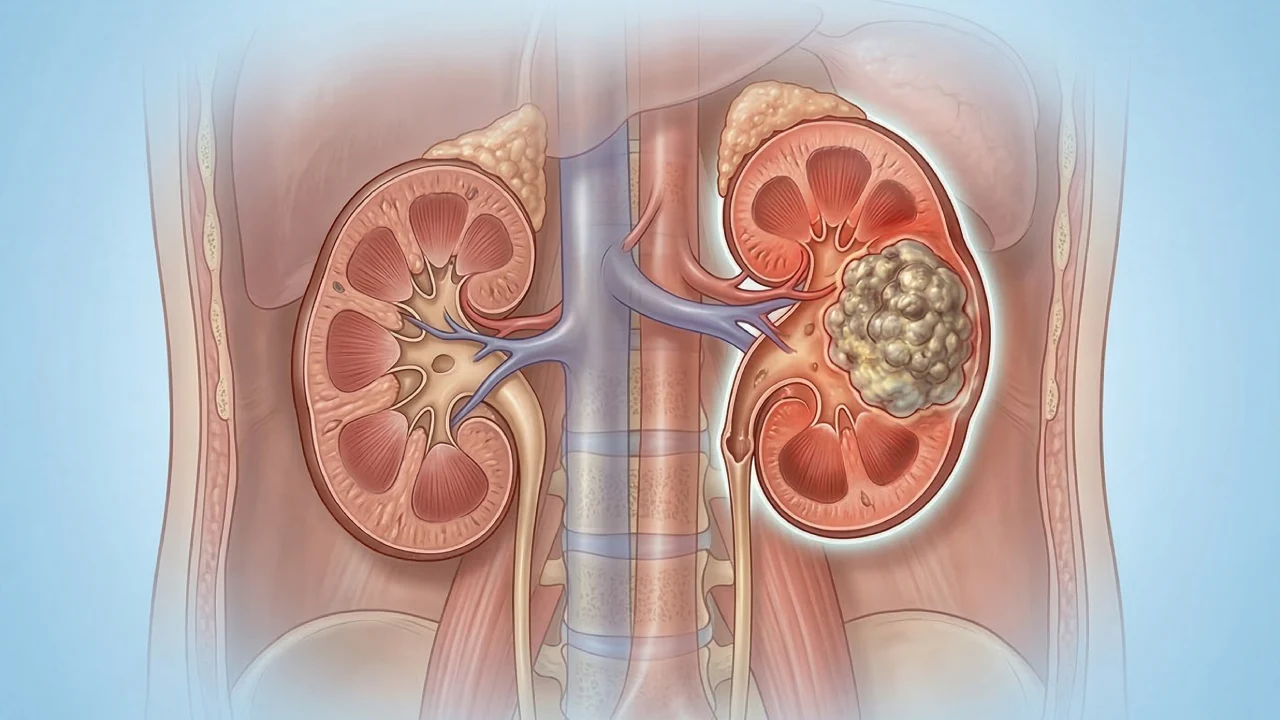

Kidney Cancer

Kidney cancer occurs when abnormal cells grow in the kidney and form a tumor.